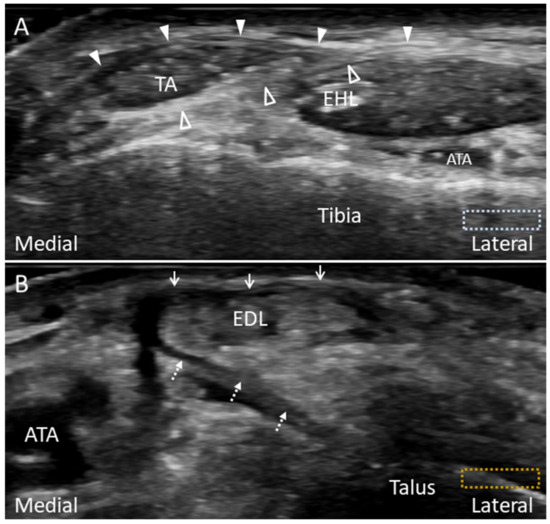

4.2. Peroneus Tertius Tendon

4.2.1. Anatomy

4.2.2. Scanning Technique

4.2.3. Clinical Relevance